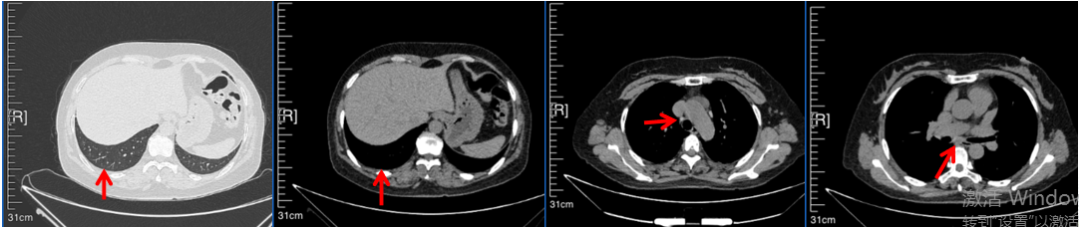

2016年1月复查CT提示支气管截断可见新发小结节,一线治疗采用培美曲塞+DDP方案化疗4周期(培美曲塞3.36,DDP 480mg)。化疗后复查胸部CT:右肺见不规则结节样影,最大层面大小约19mm*8mm,较前比较明显增大,疗效评估PD。2017.3-2017.4予单药多西他赛化疗3周期,疗效评估SD。2018年5月末复查CT提示结节较前增大,评效为PD,2018年6-10月予多西他赛+CBP化疗4周期,疗效评估SD。2022年5月患者出现活动后气短,复查胸部CT示右肺膨胀不良;右侧胸腔积液增多。胸腔积液包埋病理示符合肺腺癌细胞。行NGS基因检测:EML4:exon13-ALK:exon20融合。PD-L1(克隆号22C3)TPS<1%。

2018.07

2022.05

2022.08

2023.05

2024.12